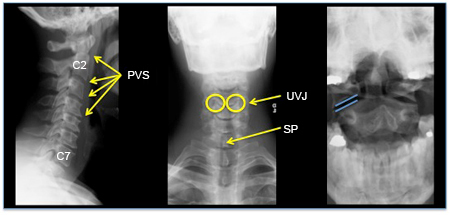

Columna cervical normal: proyección lateral, AP y de apófisis odontoides con la boca abierta